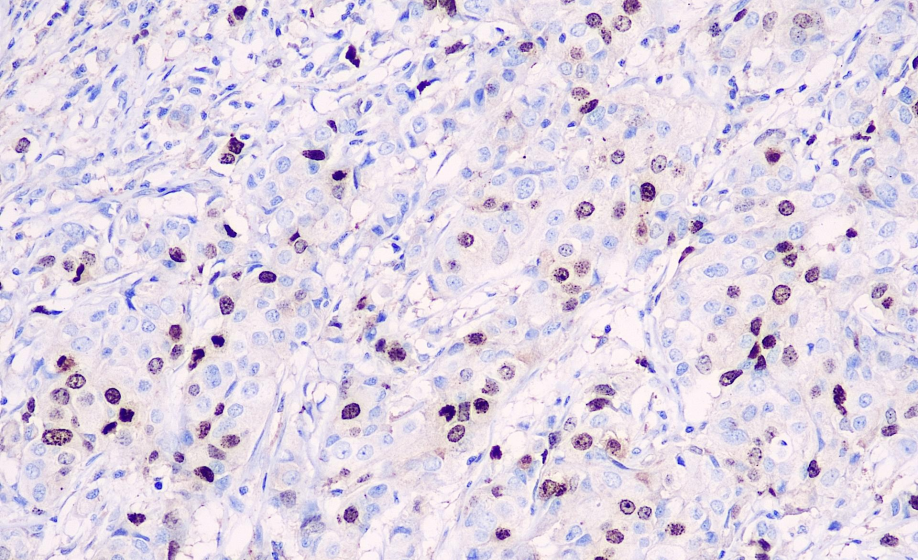

Positive control: Breast cancer

Survivin is a member of the apoptosis-inhibiting gene family, found exclusively in mammals, and is primarily expressed during the G2/M phase of the cell cycle. It participates in the regulation of the cell cycle by inhibiting the activity of apoptosis-related proteases 3 and 7, thereby preventing cell apoptosis. It is overexpressed in many malignant tumor tissues but not expressed in normal adult tissues, and is primarily used in the study of various malignant tumors. In neuroblastoma, the expression of survivin indicates a poor prognosis and lower survival rates. In gastrointestinal tumors, it is associated with abnormal expression of Bcl-2 and p53. In esophageal cancer, survivin can serve as a reference for poor response to chemotherapy.

Survivin antibody reagents can specifically bind to Survivin molecular antigens. Immunohistochemistry kits containing Survivin antibody reagents are suitable for the prognostic assessment of tumors (such as breast cancer, colorectal cancer, and lung cancer).